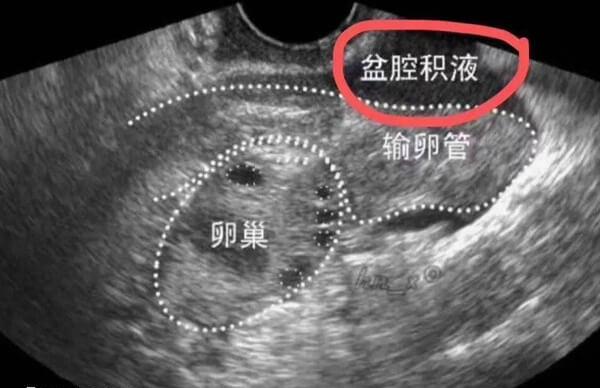

取卵手术后b超监测到盆腔积液50mm会不会自愈,需要辩证对待。如果是生理性盆腔积液月经血液逆流以及便秘时肠液渗出等因素引起,一般不需要进行特殊治疗,如果是感染以及肿瘤引起的,就是病理性盆腔积液,需要引起重视,一般不能自愈。盆腔积液可以自愈,在取卵后会自行清除,但也不排除腹水太多甚至会逐渐加重的情况,需要积极治疗。

女性在取卵后可能会检查到这样那样的问题,如果发现盆腔积液50mm难免会比较担心会不会影响后期胚胎移植和胎儿生长发育,其实针对取卵后的盆腔积液,大家也不要过于焦虑,有的人可以自愈,而一些人可以治愈。

取卵后盆腔积液是生理性的,一般不用进行特殊的治疗,因为一些女性在取卵之前,盆腔当中就会有少量的积液,这是正常的生理现象,而取完卵子之后,盆腔积液也会仍然存在生理性的盆腔积液。不用特殊处理,随着生理周期的逐渐变化会慢慢消失,不会对身体健康造成不良影响。

盆腔积液是由于外界刺激或感染等引起的,会存在需要治愈的情况。发现有病理性盆腔积液之后,要早期抗感染进行治疗,防止感染物进一步扩散。患者应该去医院,在专业医生的指导下进行治疗。在饮食方面也要以清淡为主,尽量不要吃辛辣、刺激、油腻性的食物。

总的看来,取卵手术后b超监测到盆腔积液50mm会不会自愈有两种情况,一种是生理性盆腔积液,另一种是病理性盆腔积液,前者随着时间的推移会自己痊愈,后者需要进行专业的治疗,才能治愈。如果是发现自身有盆腔积液,务必要做好个人卫生,勤换内衣裤,在平时饮食方面应该以清淡为主,增加自身营养,判断清楚是哪一种盆腔积液。